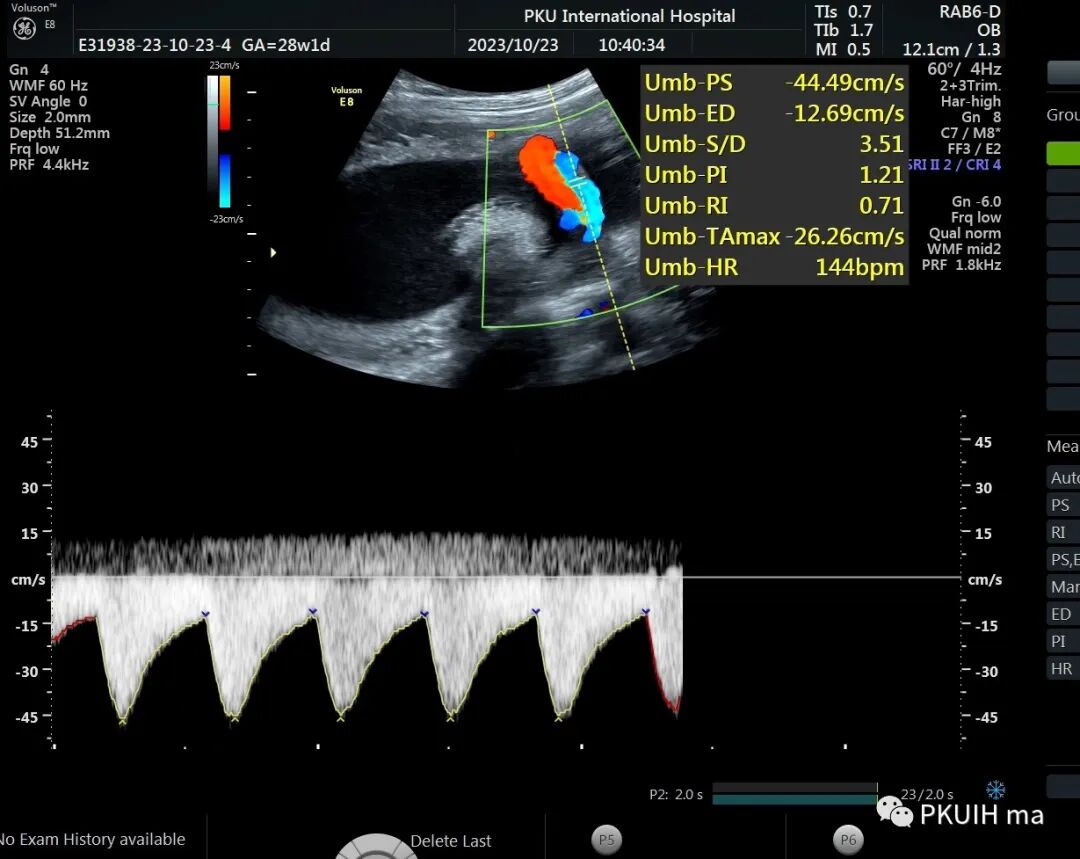

第一例是28周1天,脐动脉S/D值3.51,明显大于3。把脐血流值输入机器内,运用机器内国际指南标准,在设备内并没有S/D参数参考,而是采用脐动搏动动指数(PI)和阻力指数(RI)脐动脉的阻力在正常范围内(5-95%区间)